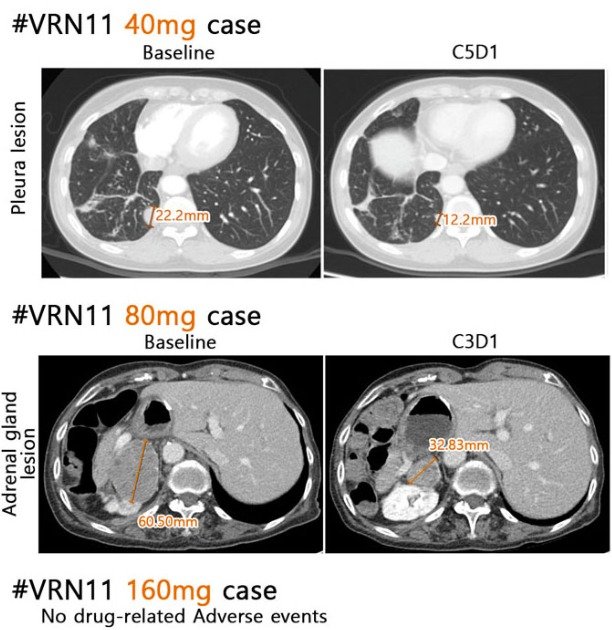

보로노이 4세대 폐암 신약 후보물질 'VRN11' 용량별 투여 결과. 병변이 줄어 들고 별다른 부작용이 확인되지 않았다.(보로노이 제공)/뉴스1

효능 평가 결과 기존 표준 치료요법으로 치료한 후 C797S 돌연변이가 나타난 환자를 대상으로 VRN11 40㎎를 투약한 결과 4주 후 종양이 40% 이상 감소했다. Del19 돌연변이 환자를 대상으로 80㎎를 활용해 치료한 3주 후에는 종양이 20% 이상 줄었다.